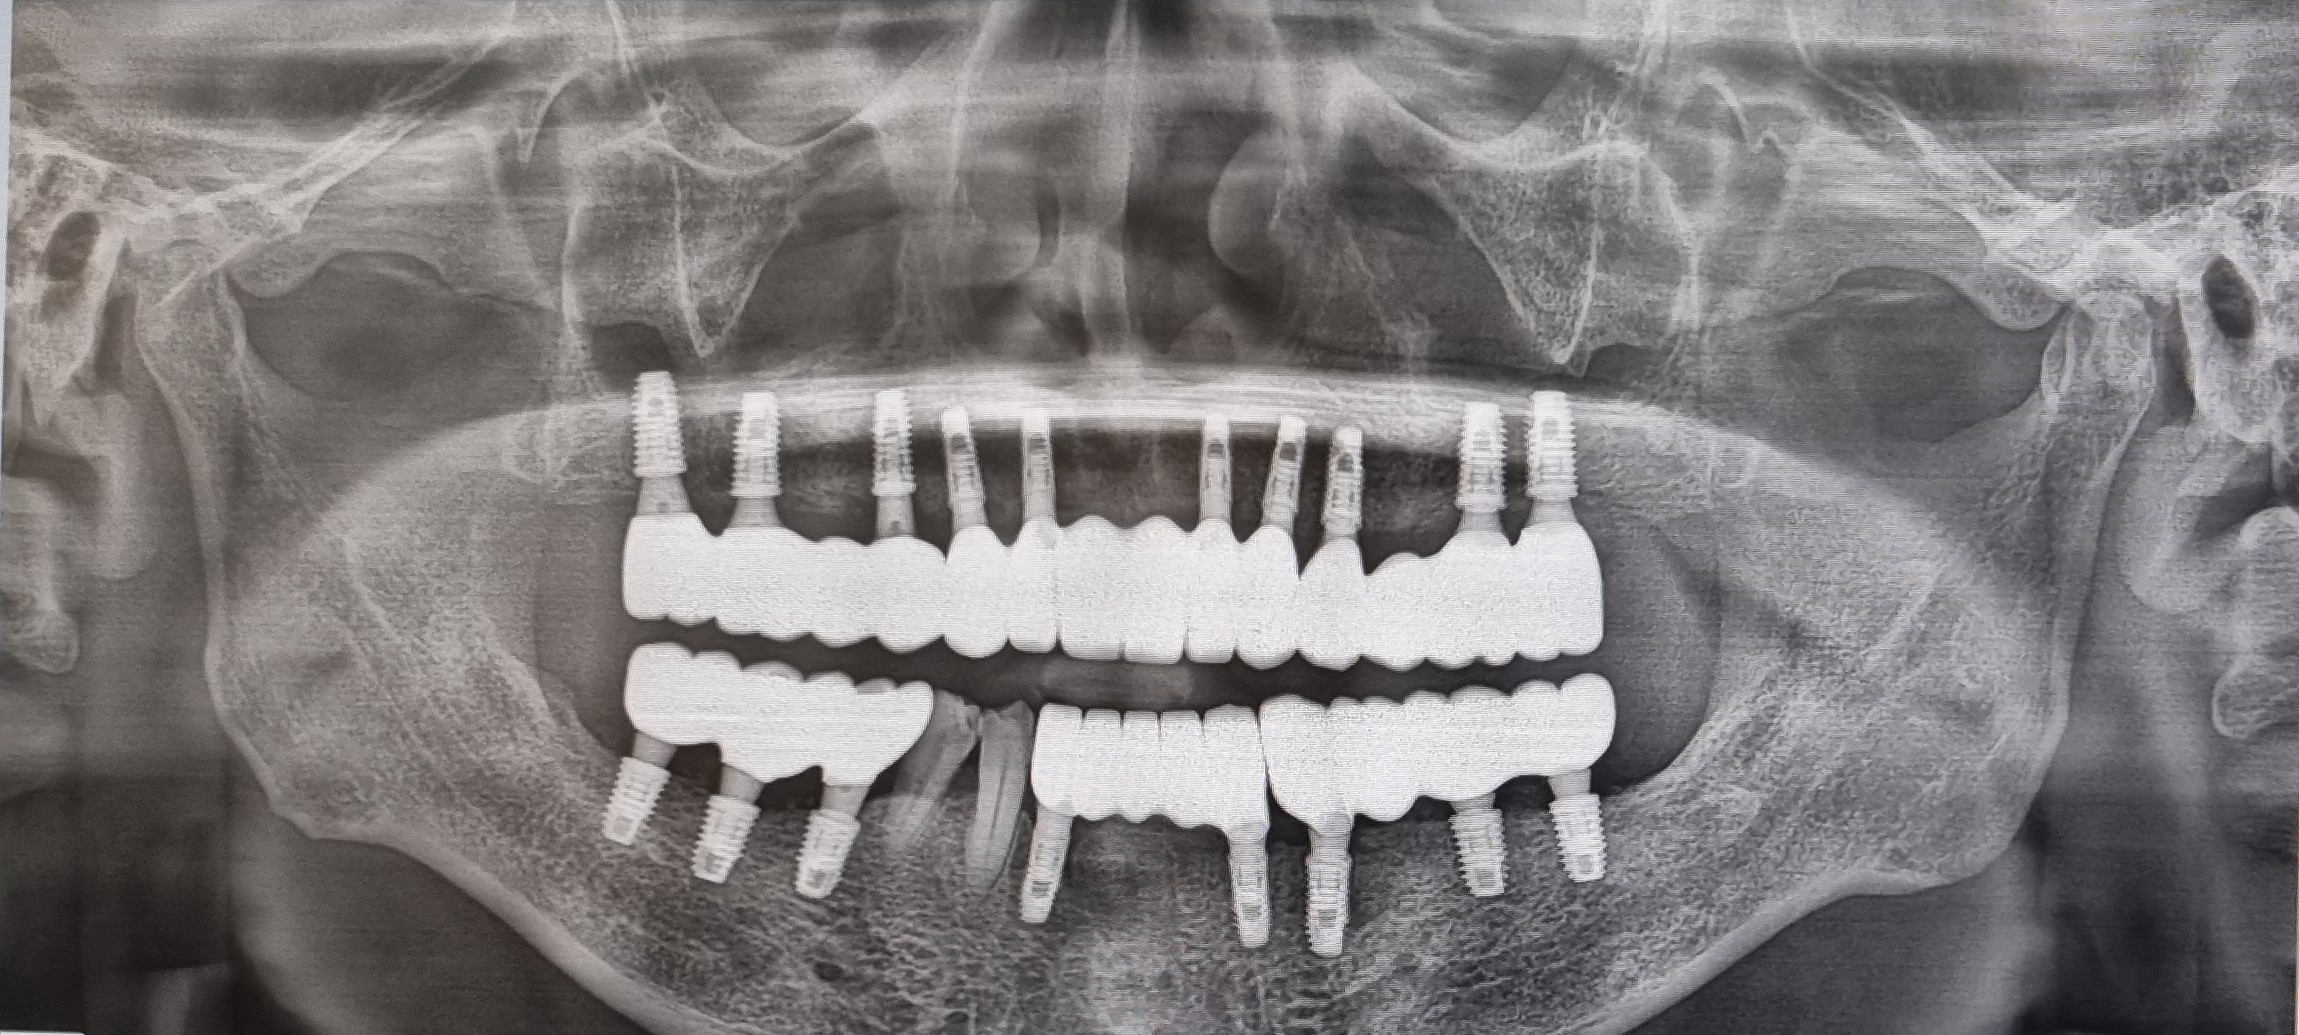

CT 촬영을 통해 구강口腔健康내  상태등을  검사하고  윗턱의  경우  모두  치아齒牙

치주염 齒周炎으로 인하여 결손된 상태라서 자연치아齒牙 2개와

전체  임플란트dental implant와  브릿지bridge를 같이  결합하여

전체  임플란트dental implant의 개수를  낮추는 방향으로  진행 하엿습니다.

임플란트dental implant를  윗니上顎 Over Denture 10   아랫니 下顎 치아齒牙 2 개를

제외하고 대부분의  치아齒牙  치주염 齒周炎 으로  좋지않은  상황이라

발치拔齒 뼈이식과  임플란트 8개를 식립植粒하기로 했습니다.

임플란트dental implant 18개을 식립植粒하는  수술이고.

1 上顎 Over Denture 76 X  32 X   X 23    4 X 67    10

下顎 765       1      XX 3   4 X 67      8

이제  윗니上顎 10X-ray 이미지에서도 모두 1차  수술  치료가  깔끔하게  긑낫습니다.